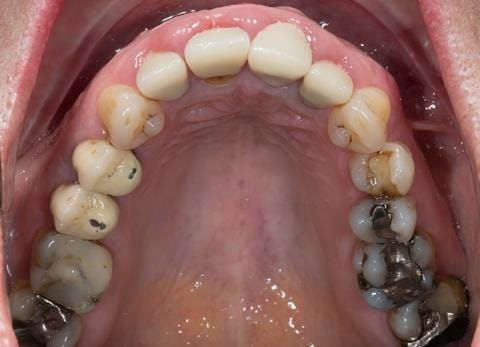

- UR2 peri-radicular periodontitis with a peri-radicular area on the root apex. Retrograde amalgam filling from a previous apicectomy. No visible root canal or root canal filling. Large circumferential marginal gap between the crown and tooth. Large post and core present. Very little tooth structure remaining resulting in a fragile tooth with increased potential for fracture.

- UR1 peri-radicular periodontitis with a small peri-radicular area on the root apex with wide blunderbuss apex. Radio-opaque root canal filling present approximately 3 mm short of the radiographic apex. Large circumferential marginal gap between the crown and tooth. Large post and core present. Very little tooth structure remaining resulting in a fragile tooth with increased potential for fracture.

- UL1 peri-radicular periodontitis with a peri-radicular area on the root apex. Retrograde amalgam filling from a previous apicectomy. Visible root canal space with no sign of root canal filling. Large circumferential marginal gap between the crown and tooth. Large post and core present. Very little tooth structure remaining resulting in a fragile tooth with increased potential for fracture.

- UL2 peri-radicular periodontitis with a peri-radicular area on the root apex. No visible root canal or root canal filling. Large circumferential marginal gap between the crown and tooth. Large post and core present. Very little tooth structure remaining resulting in a fragile tooth with increased potential for fracture.

- High smile line showing gum above gingival zeniths of upper front teeth when smiling. Aesthetic failure of the upper four incisors with inflammation of the gingivae and mis-match of the gingival zenith levels.

- Other than the maxillary incisors the remaining dentition was in marginally better condition being moderately to heavily restored. Many will probably require replacement and restoration from time to time mainly from wear and tear owing to occlusal forces.